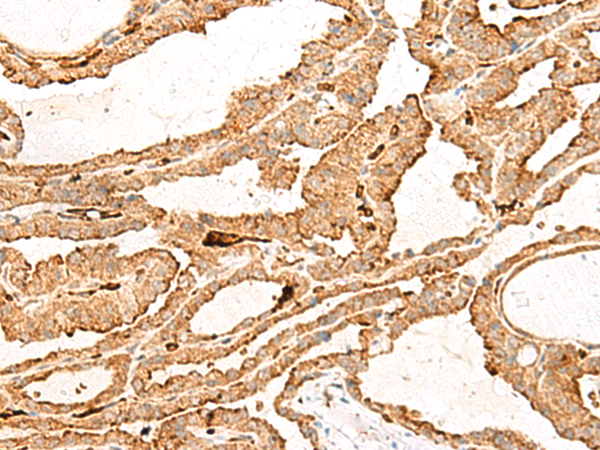

IHC positive control:

Human thyroid cancer

IHC Recommend dilution:

40-200